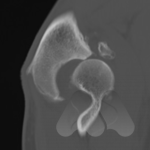

Dislocations are commonly a result of trauma causing the joint to move out of its normal position and relationship with other bones. Dislocations can be accompanied by fractures. Sometimes the dislocation causes an obvious deformity and can be pulled or pops back into position on it’s own. In some situations, the joint cannot be pulled back into position or keeps falling out of position due to tissues such as bone fragments blocking the reduction or due to torn ligaments or fracture through supporting bones. In this situation, you may need to have some form of anaesthetic to realign the bones in the Emergency department or operating theatre or in some cases, the joint being opened and surgically stabilised.